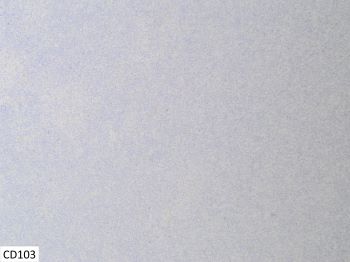

Distinct immunophenotypic features further distinguish MEITL and EATL, including but not limited to differing expression of CD56 and CD103. MEITL is CD56 positive in most cases, while EATL is CD56 negative. For CD103, EATL is CD103 positive, while MEITL shows variable expression of CD103 and often negative. For this case, the results of CD56 and CD103 immunohistochemical stains seen in the provided images results are compatible with MEITL.